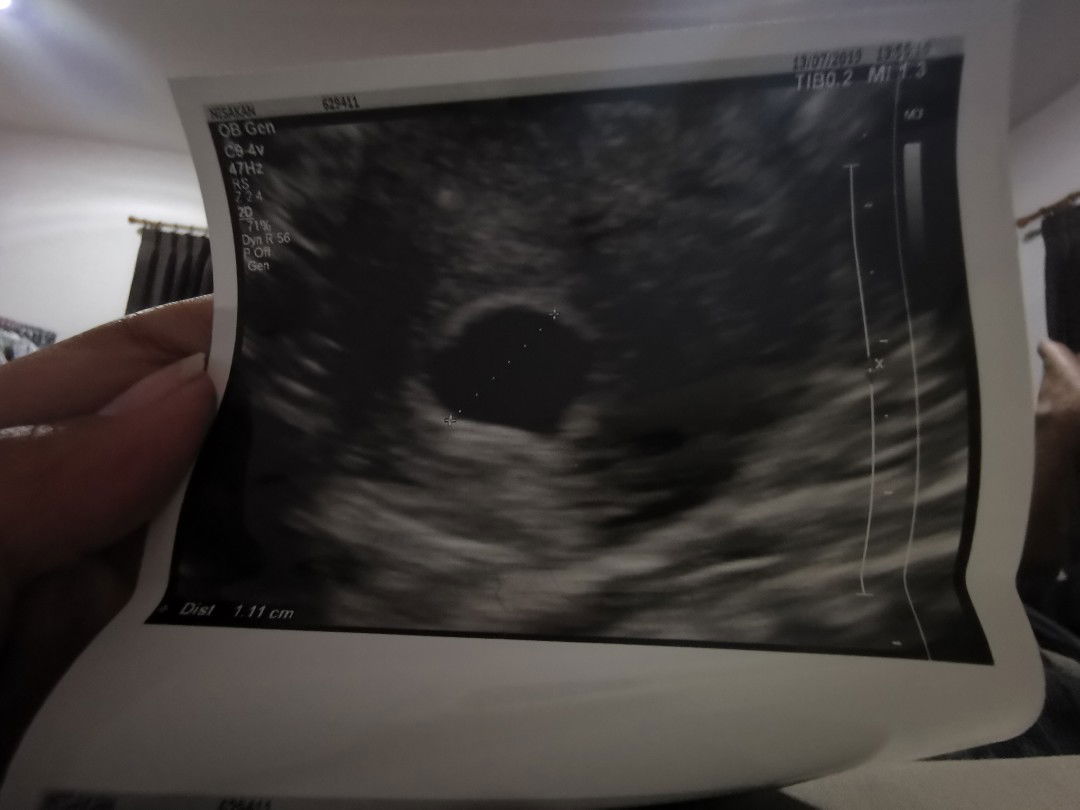

มีใครเคยไปอัลตร้าซาวด์ 2 ที่ ในระยะเวลา ใกล้ๆกันไหม พอดีเราไปซาวด์ครั้งแรก ลืมเอาแว่นไป มองไม่ค่อยเห็นเด็ก แต่คุณหมอบอกว่า ตั้งครรภ์ 6week 1day และได้ฝากครรภ์กับที่แรกไปแล้ว แต่หลังจากนั้น ครบ7 week เราได้ไปอัลตร้าซาวด์ อีกคลินิกนึง หมอบอกไม่พบเด็ก และบอกว่าอายุครรภ์แค่ 6week งั้นเราควรจะเชื่อที่ไหนดี กังวลไปอีก กลัวจะท้องลม เราอัลตร้าซาวด์ผ่านช่องคลอดทั้ง 2 ที่้เลยนะคะ เป็นที่เครื่องอัลจร้าซาวด์หรือป่าวนะ ใครเคยเจอแบบนี้บ้างคะ #ขอคำแนะนำหน่อยค่ะ #ขอบคุณสำหรับคำตอบค่ะ #ใครมีประสบการณ์